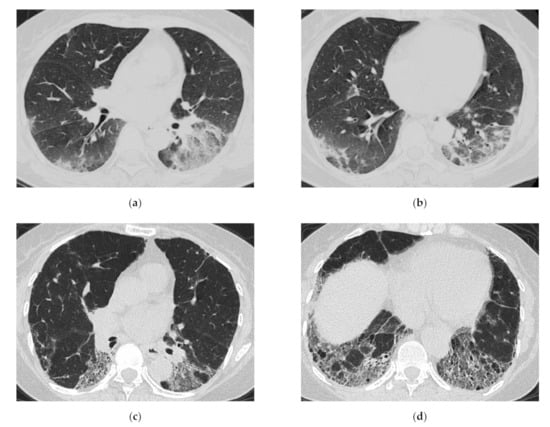

3.1. Anti-Aminoacyl tRNA Synthetase Antibody (Anti-ARS Ab)

HRCT Findings of Patients with Anti-ARS Ab

3.2. Anti-MDA5 Antibody (Anti-MDA5 Ab)

HRCT Findings of Patients with Anti-MDA5 Ab